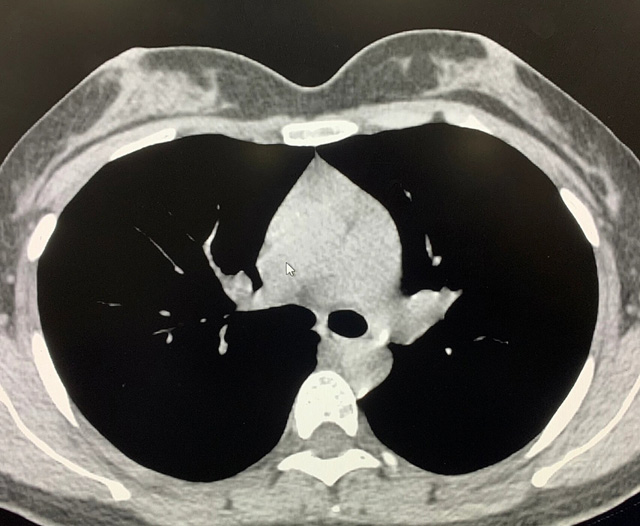

能譜純化技術(shù)的核心是通過物理濾過(如錫濾片)或軟件算法,選擇性濾除低能X射線光子,保留高能光子。在胸部低劑量CT掃描中顯著提升了圖像質(zhì)量與輻射劑量的平衡。

優(yōu)勢輻射劑量顯著降低相較于常規(guī)CT,輻射劑量減少約70%-90%,尤其適合需多次隨訪的高危人群(如肺癌篩查),降低輻射相關(guān)癌癥風(fēng)險(xiǎn)早期肺癌篩查效果明確可清晰檢測毫米級肺結(jié)節(jié),顯著提高早期肺癌檢出率,降低死亡率。檢查快捷且普及性高單次掃描僅需數(shù)秒,無需對比劑,設(shè)備廣泛配置于基層醫(yī)院,便于大規(guī)模篩查。長期成本效益顯著雖單次費(fèi)用與常規(guī)CT相近,但早期干預(yù)可大幅降低晚期治療費(fèi)用及社會醫(yī)療負(fù)擔(dān)。技術(shù)優(yōu)化提升圖像質(zhì)量迭代重建算法(如ASIR、MBIR)在降低劑量同時減少噪聲,平衡影像質(zhì)量與安全性。